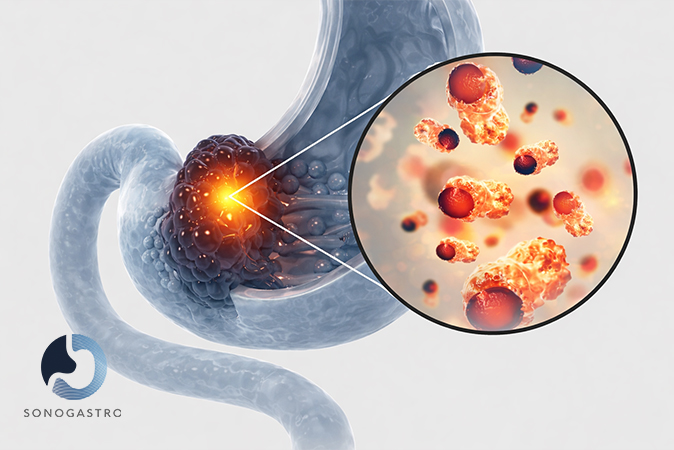

Upper Digestive Conditions

Chronic gastritis

Acid reflux (GERD)

Persistent heartburn

Helicobacter pylori infection

Esophagitis

Peptic Ulcer Disease

Barrett's Esophagus

Celiac Disease